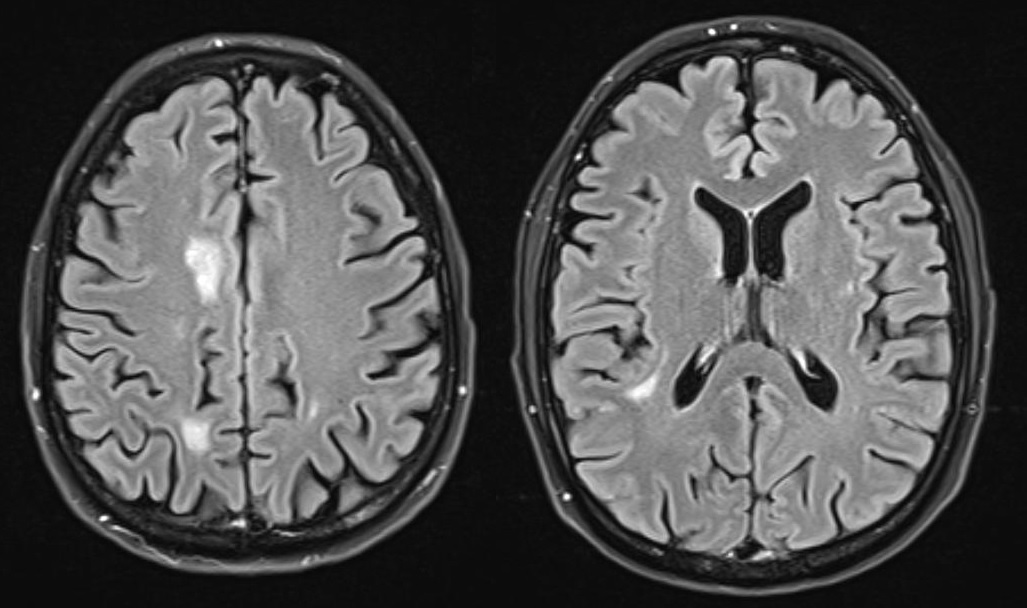

Case presentation: A 39-year-old man was initially diagnosed with lung cancer based on computed tomography and histopathologic findings. He was treated with 2 lines of chemotherapy over an 8-month period, the neoplastic lung lesions progressed, and he was referred to palliative care. Two years after his initial diagnosis, during the management of an actively bleeding gastric tumor, he was diagnosed with HIV and referred to an infectious disease unit. Immediate antiretroviral treatment was initiated after diagnosis, and further evaluation confirmed the presence of B-cell lymphoma. A retrospective review suggested that the initial cancer diagnosis was likely misinterpreted and was in fact lymphoma, a malignancy commonly associated with HIV. Lymphoma treatment was initiated, and after 1 year, the patient achieved HIV-1 virologic suppression and near-complete remission of all lesions.